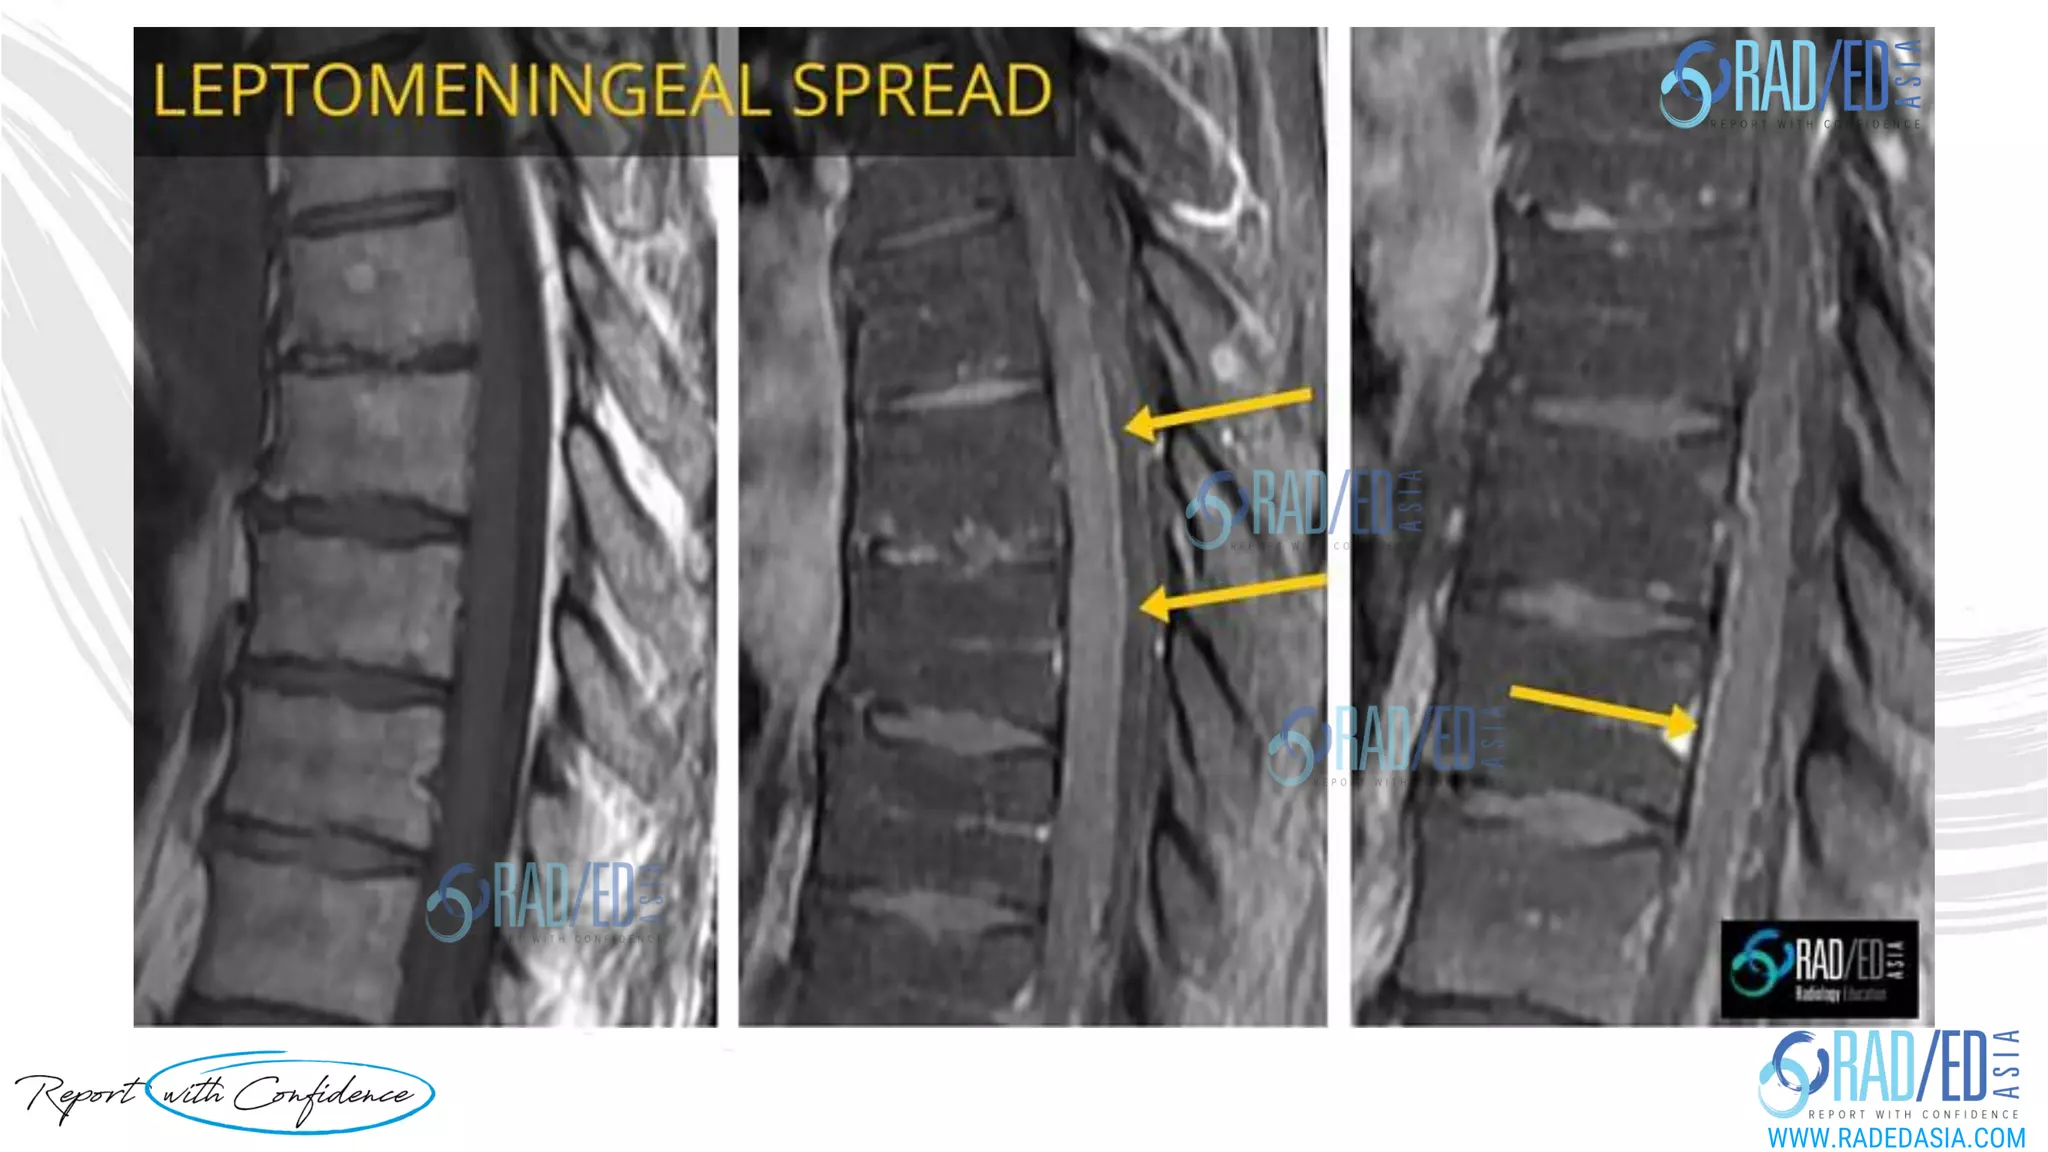

Cord compression MRI. When to give contrast MRI in patients with known tumour and what's the important sequence to perform that sometimes is not routinely done. In a patient with known malignancy who comes in for ? Cord compression, its not uncommon to see contrast not given if the initial screening scans demonstrate no evidence of extrinsic compression. However leptomeningeal spread which may be the cause of the patients symptoms may not be seen on non contrast scans. The images demonstrate leptomeningeal spread seen only on the contrast scans, and no extrinsic compression, in two patients who came in with a known breast carcinoma with a suspicion of cord compression. When do we give contrast and what's the most important sequence to perform. We discuss this in more detail at this link : http://bit.ly/learnmricordcompression All our MRI Mini Fellowships at this link: http://bit.ly/radiologyonline #radedasia